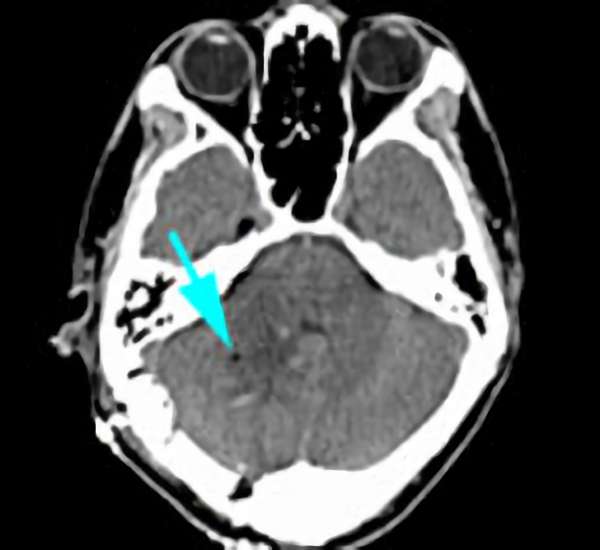

'25年10月

40代

南田,野本,元永

脳幹部

海綿状血管腫

出血の予防目的

熊本県の病院

No.No.62 手術前1

No.No.62 手術前2

No.No.62 手術後1

No.No.62 手術後2

CT/MRにより完全に摘出されたことが確認された